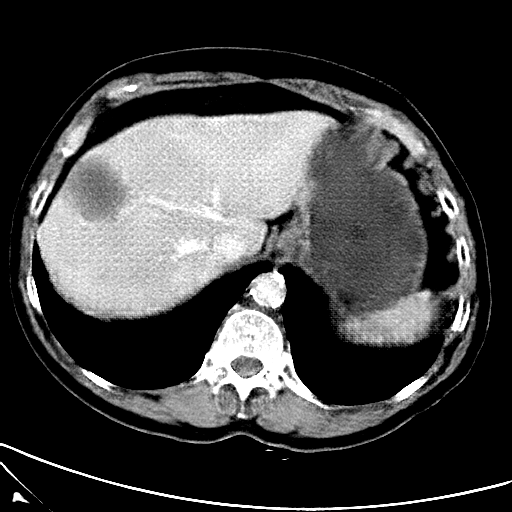

Refer to caption

(a) CT images.

(b) MRI images.

Figure 6: Lossy compression based attack on CT images (a) and MRI images (b) with a specific channel numbers (C8050\mathrm{C^{50}_{80}}) for the EP and IT Scenarios. StolenEPD1\mathrm{Stolen}^{\mathrm{D1}}_{\mathrm{EP}} denotes the decompressed images in the EP Scenario with a reduced D1 decoder.

Compression-Fidelity Compromise. Based on the previous results, we have selected the decoder D1D1 and the configuration of the latent and hyperlatent variables C8050\mathrm{C^{50}_{80}}, as the optimal architecture of the HiFiC encoder-decoder pair. In Fig. 6, we display more specifically the compression and reconstruction quality performances. In terms of reconstruction quality, we obtain a PSNR of approximately 40 for CT images and around 38 for MRI images while the MS_SSIM values are close to 1. This indicates an excellent perceptual quality of the reconstructed images that are hardly discernible from the original ones. In terms of compression efficiency, the Pratio\mathrm{P}_{\mathrm{ratio}} for CT images is approximately 0.015, indicating that the lossy image compression-based attack generated compressed images are 67 times smaller than those produced by the lossless zipped image compression-based attack. For MRI images, the Pratio\mathrm{P}_{\mathrm{ratio}} is around 0.12, 10 times higher than that of CT images, which can be attributed to the presence of a large uniform background in the skull-stripped original MR images.